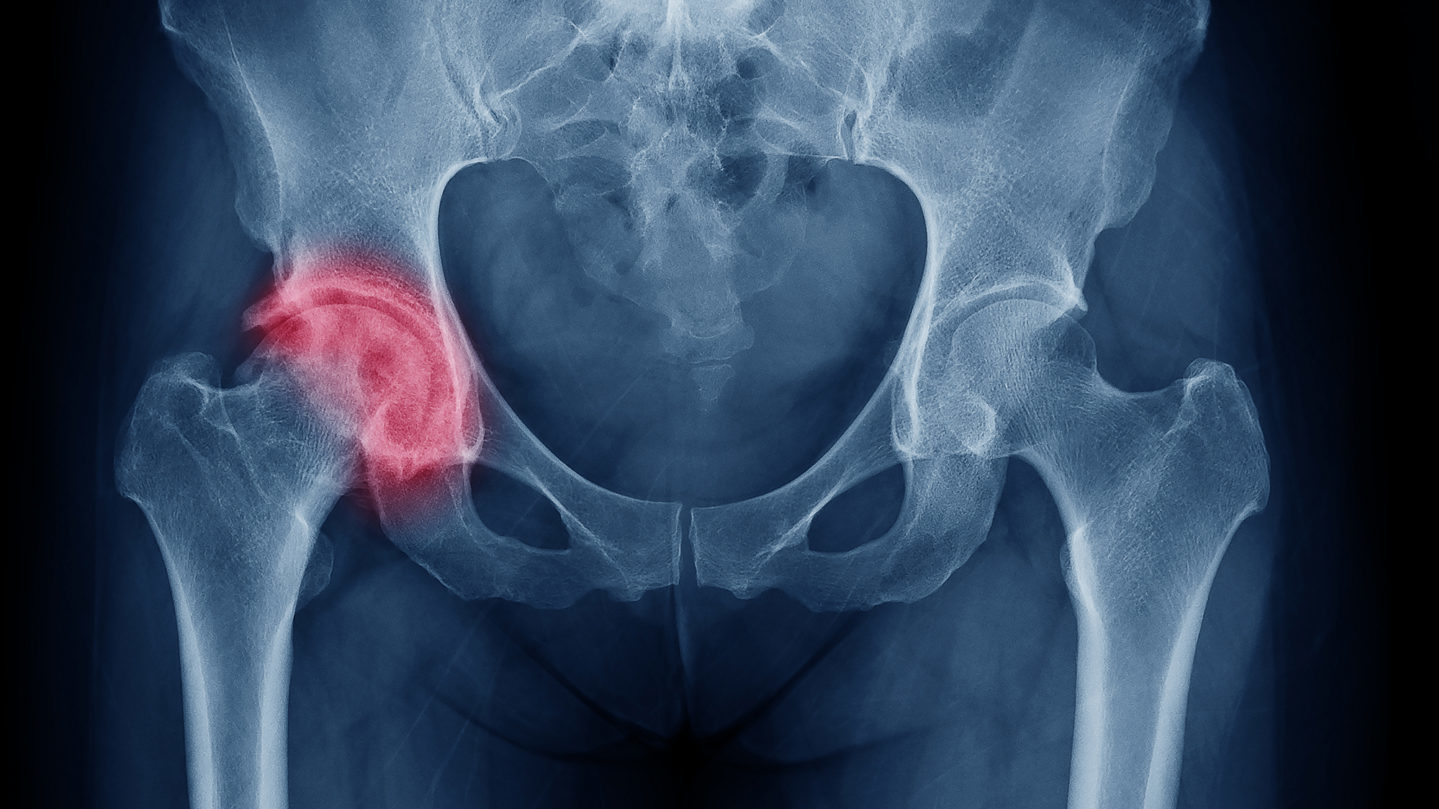

Yaşlılarda Kalça Çıkığı

Kalça ekleminin yerinden kayması durumudur. Yaşlılarda kalça çıkığı genellikle düşme, travma veya osteoporoz gibi kemik zayıflıkları sonucu oluşur. Kalça eklemindeki bağlar ve kaslar zayıflar, bu da çıkık riskini artırır. Hastalar şiddetli ağrı, hareket kısıtlılığı ve yürüme zorluğu yaşar. Tedavi genellikle cerrahi müdahale ve fizik tedavi gerektirir. Erken müdahale, iyileşme sürecini